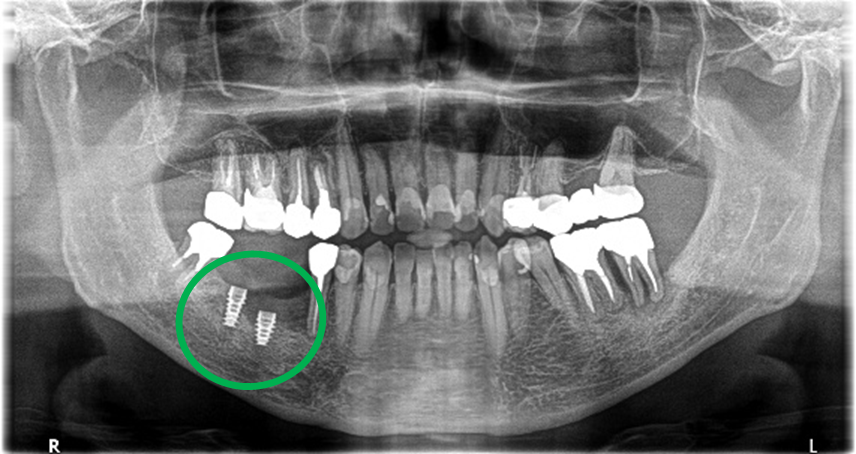

男性 Eさん 80代 (インプラント)

主訴

左上2本が動いていて、噛むと痛みがある。歯がないところに歯を入れたい。

治療内容

左上第二小臼歯と第一大臼歯の歯根が破折していたため、保存することができず抜歯しました。第一小臼歯は、すでにありませんでしたので、2本抜歯後3本欠損のところにインプラントを2本埋入しました。

所感

2006年10月に右下と左下の欠損部分にインプラント治療をしました。今回も左上の歯を失ったところは、インプラント治療を希望されました。

インプラント2本:¥363,000✕2本=¥726,000(税込)

ポンティック1本:¥115,500(税込)

合計:¥841,500(税込)

Before

※赤丸は、歯根が破折していたため抜歯しました

※黄色丸は、2006年10月に埋入したインプラント

After

※緑丸は、今回埋入したインプラント